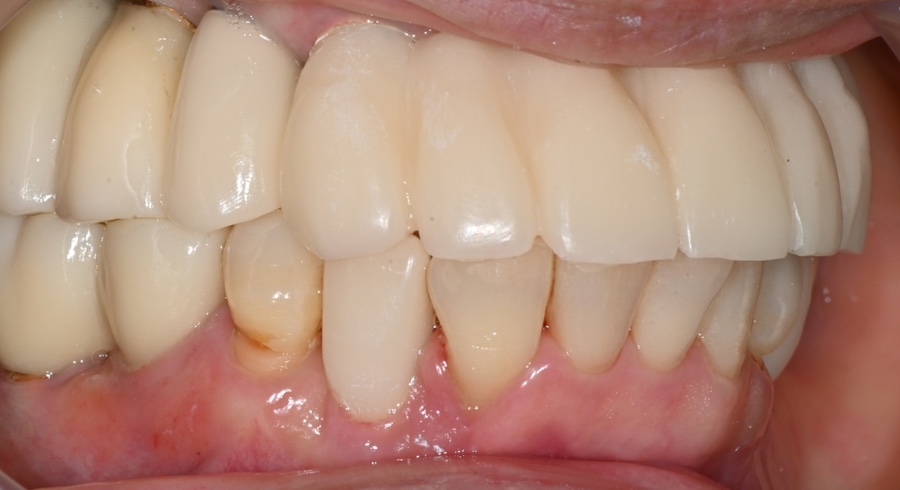

최종 지르코니아 보철 장착

충분한 조정을 거쳐

최종 지르코니아 보철을 장착했습니다.

앞니 라인부터 어금니 라인까지

자연스럽게 이어지도록 디자인했고,

씹는 힘이 한쪽으로 치우치지 않도록

교합을 세밀하게 조정했습니다.

이 과정에서 환자분은

“전체적으로 씹는 힘이 균형 있게 들어간다”고

말씀해주셨습니다.